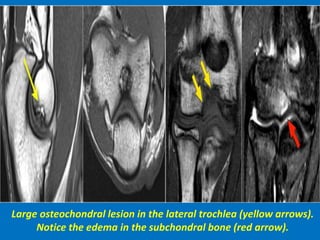

Large osteochondral lesion in the lateral trochlea (yellow arrows).

Notice the edema in the subchondral bone (red arrow).

Large osteochondral lesionin the lateral trochlea (yellow arrows). Notice the edema in the subchondral bone (red arrow).